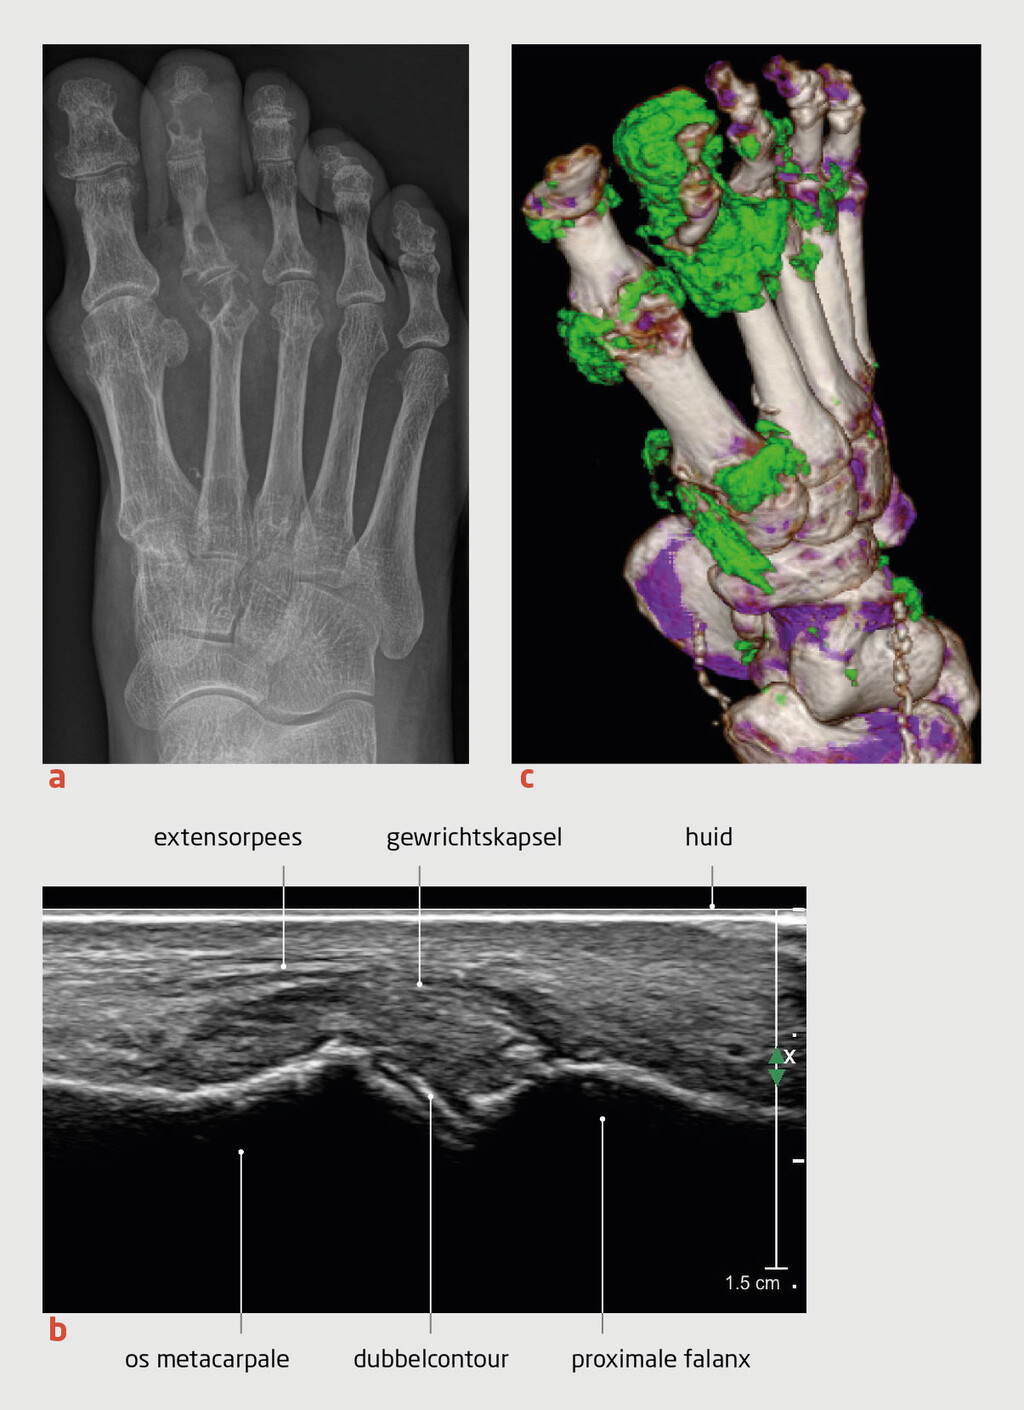

Wij erkennen dat er vanuit huisartsen zeer belangrijke wetenschappelijke bijdragen zijn geleverd aan allerlei facetten rondom jicht. Een huisarts als medeauteur had dan ook zeker niet misstaan. De aanvullende expertise van reumatologen omvat verder de diagnostiek van kristallen en de toegang tot andere dure diagnostische middelen (zoals bijvoorbeeld de DECT). Ook hier zouden wederzijdse afspraken moeten komen om de zorg nog beter af te stemmen (1).